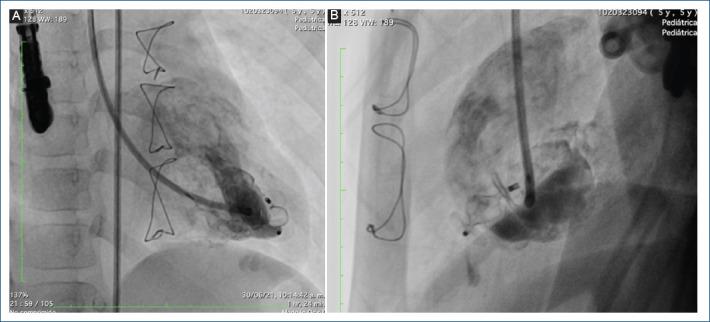

Present other management options for ventricular diverticula, different from surgical options, using alternative materials that are not used very often in daily practice.

A detailed description of a case successfully managed with these new treatment modalities.

Endovascular management of the left ventricular diverticulum, diagnosed prenatally in the patient presented, was successful after initial failure with surgical management.

提出与手术选择不同的心室憩室管理方案,使用日常实践中不常用的替代材料。

详细描述一例成功采用这些新治疗方式的病例。

本文所呈现患者产前诊断出的左心室憩室,在手术治疗初次失败后,血管内治疗取得成功。